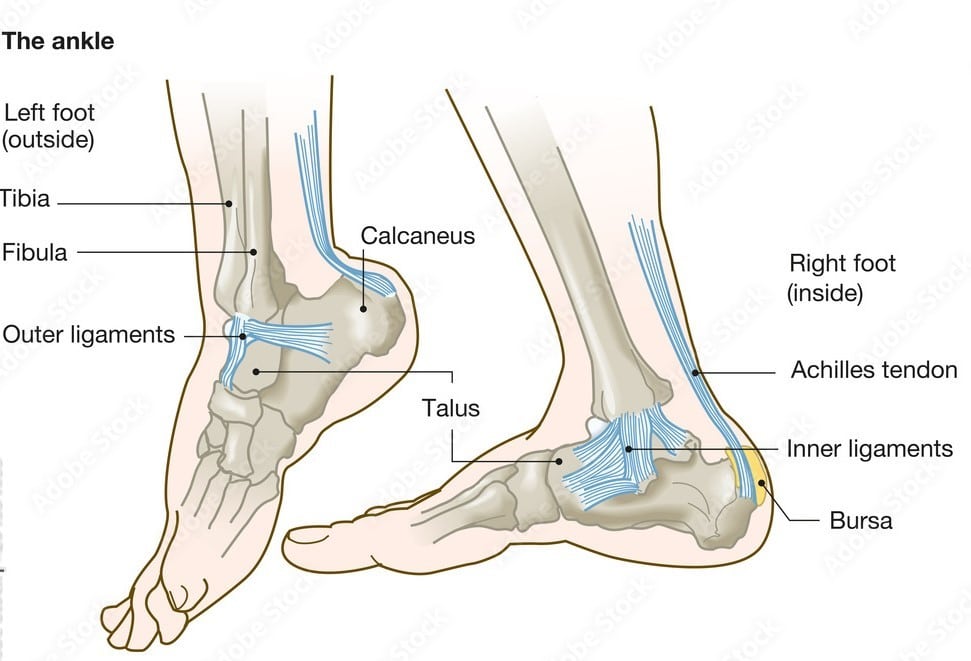

Foot and ankle services encompass comprehensive care for disorders affecting mobility, from acute injuries to chronic conditions. The complex anatomy—28 bones, numerous joints, ligaments, and tendons—demands specialized expertise for optimal outcomes.

Dr. Pradeep Kumar provides advanced management for common issues like ankle sprains, fractures, Achilles tendon ruptures, plantar fasciitis, bunions (hallux valgus), flat feet (pes planus), arthritis, diabetic foot complications, and sports injuries.